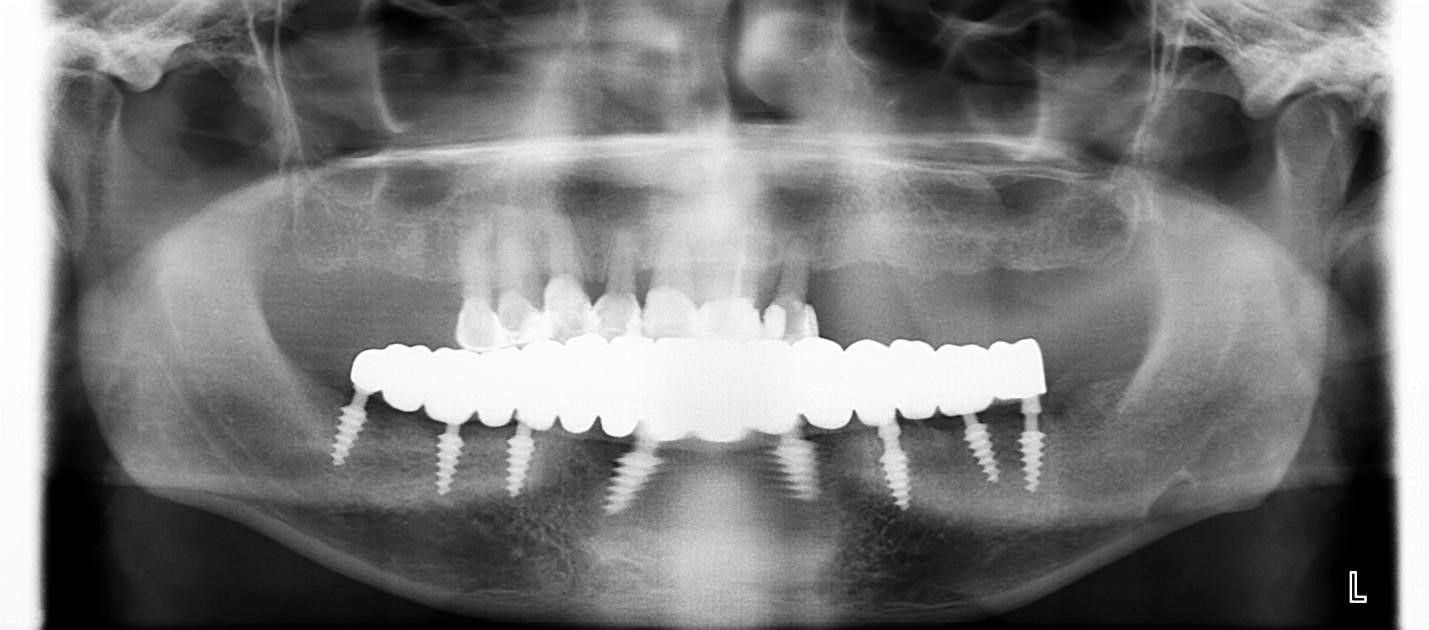

ОПГ с постоянным протезированием

Сразу после операции были сняты оттиски на временные коронки. И на третий день пациент получил временные коронки на нижней челюсти и постоянные коронки из диоксид циркония через 4 месяца. Пациент был очень доволен от такой быстрой реабилитации дентальной имплантации за такой короткий промежуток времени. Операция прошла максимально комфортно как и послеоперационный период. Мы видим 100 процентную интеграцию дентальных имплантов и блестящие отсроченные результаты.